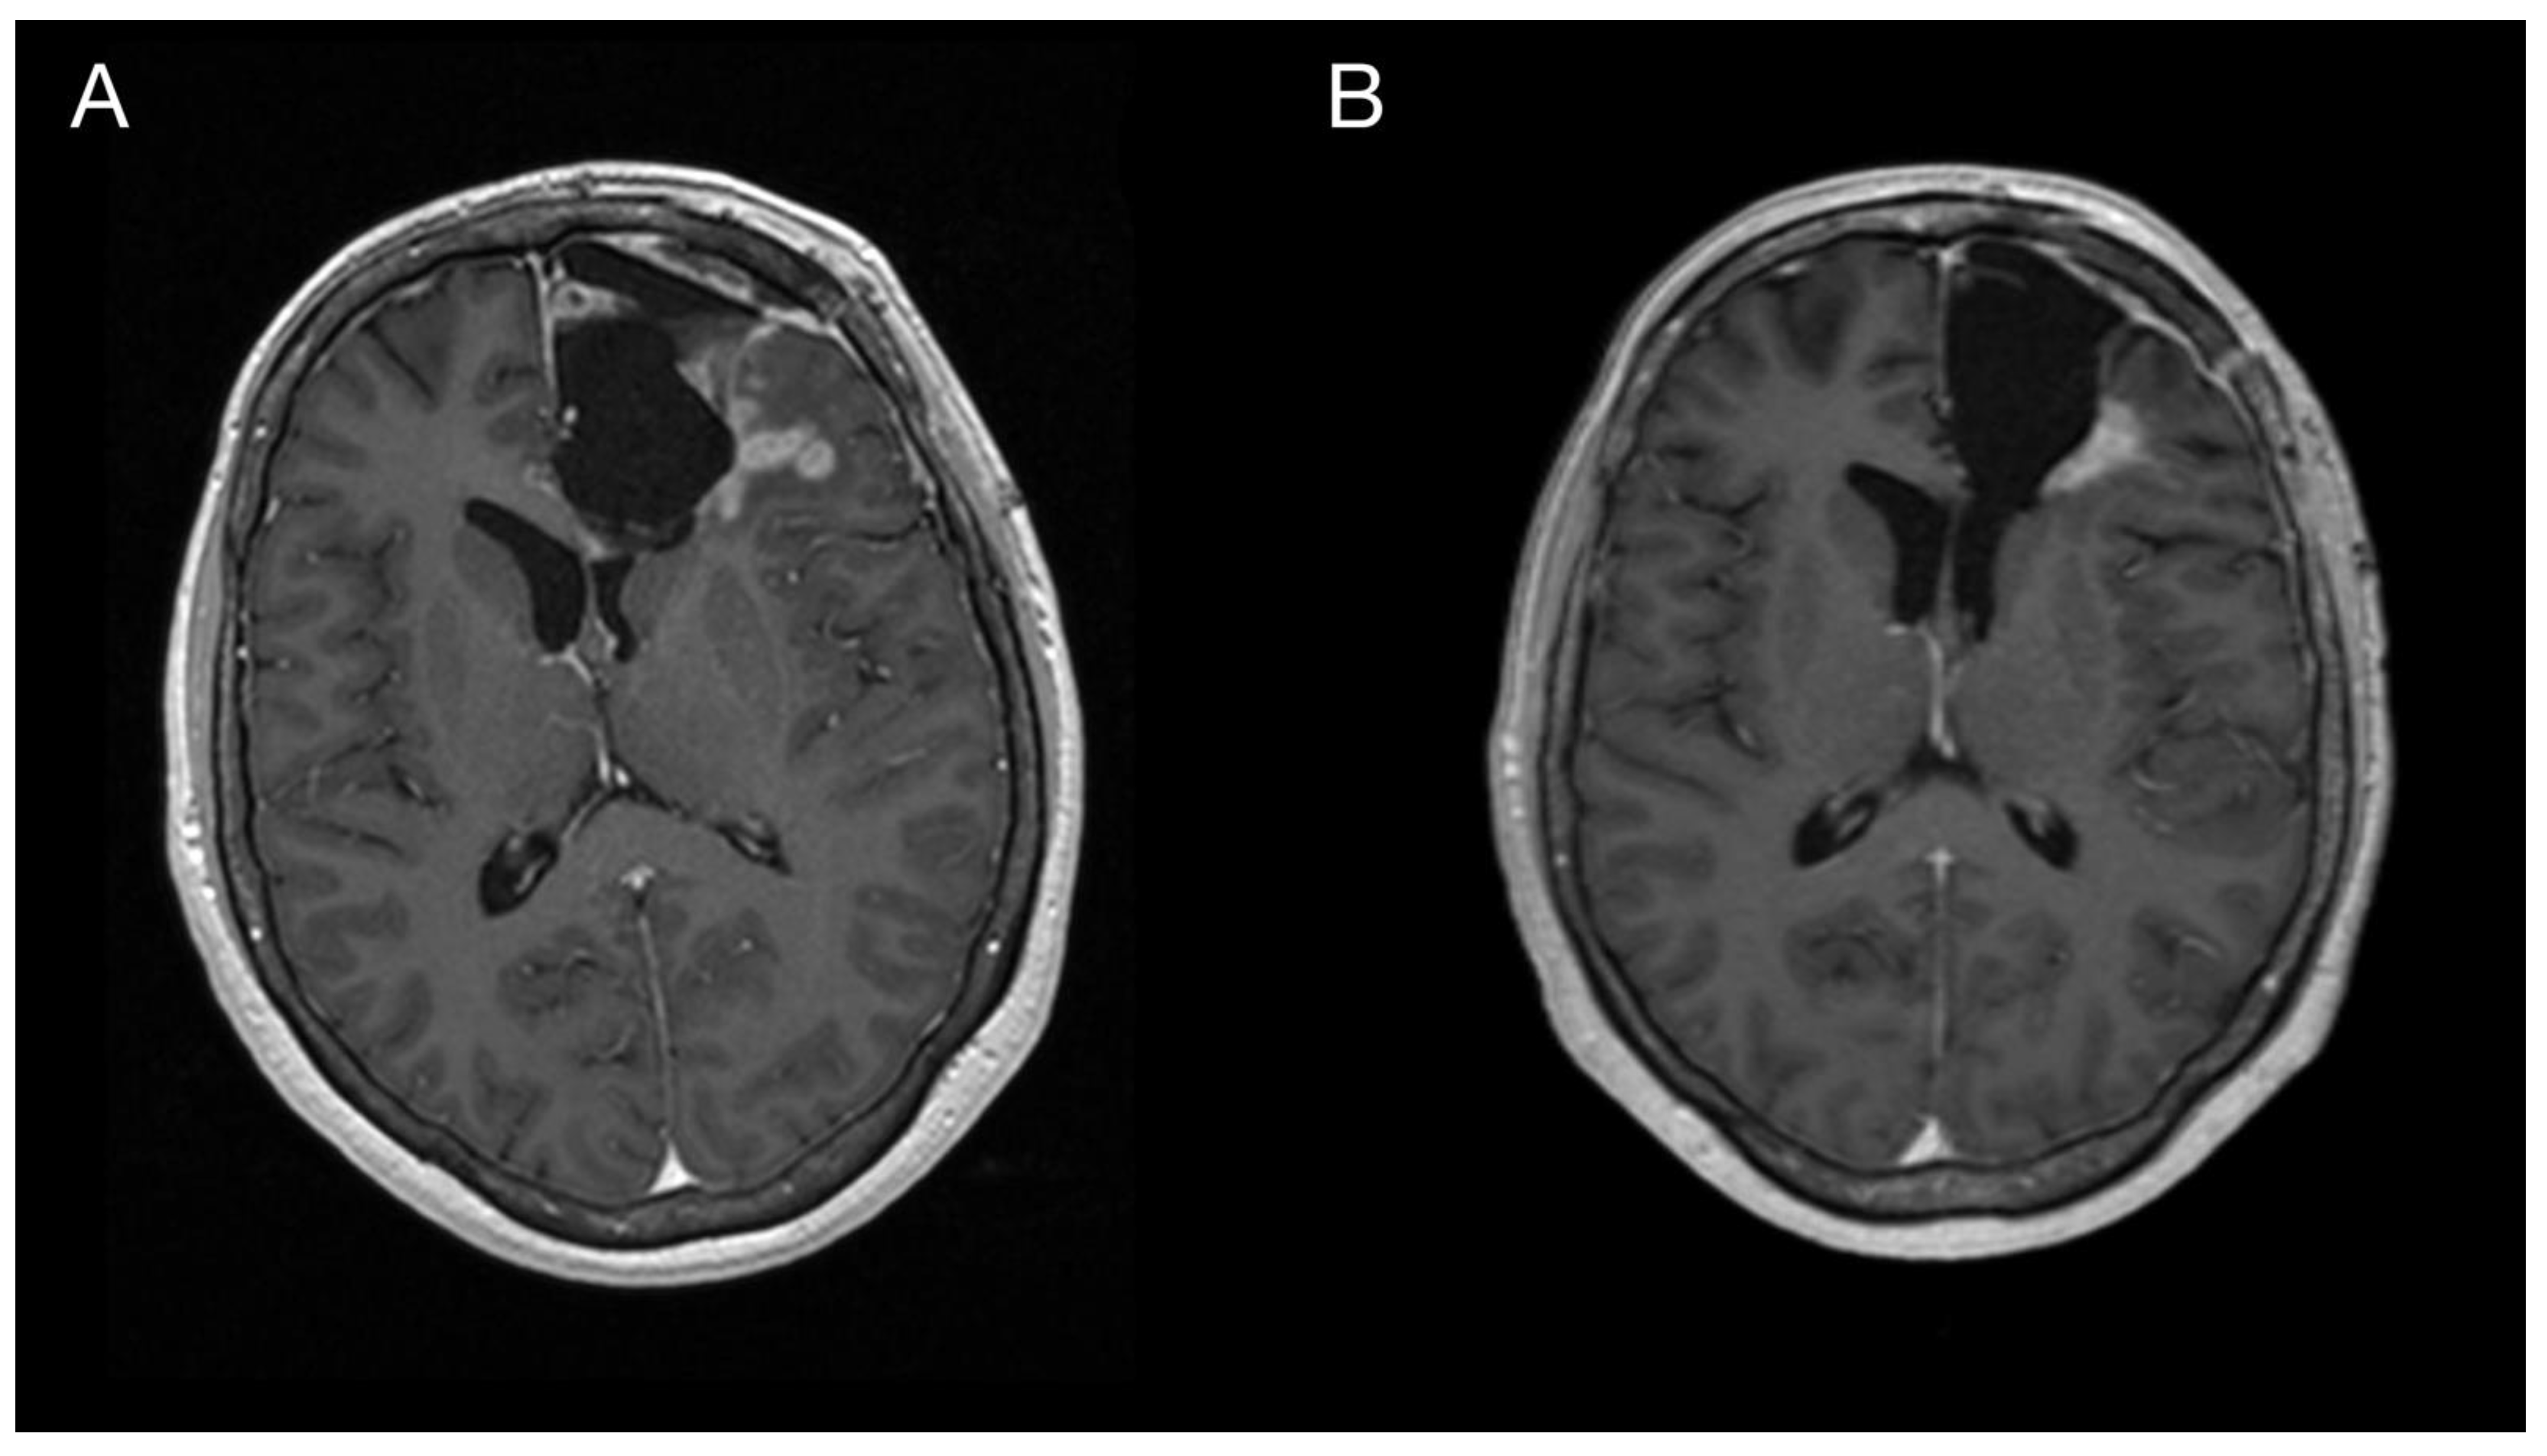

Figure 4.

Imaging of the primary brain tumor prior to and after the oncological treatment. Axial brain MRI (postcontrast T1 weighted images) prior to oncological treatment displaying GBM’s rapid early progression in the left frontal lobe (A) and two months after the chemo-radiotherapy (B).

Figure 5.

Imaging of the primary brain tumor prior to and after the oncological treatment. Axial brain MRI (fluid-attenuated inversion recovery images) prior to oncological treatment displaying GBM’s rapid early progression in the left frontal lobe (A) and two months after the chemo-radiotherapy (B).